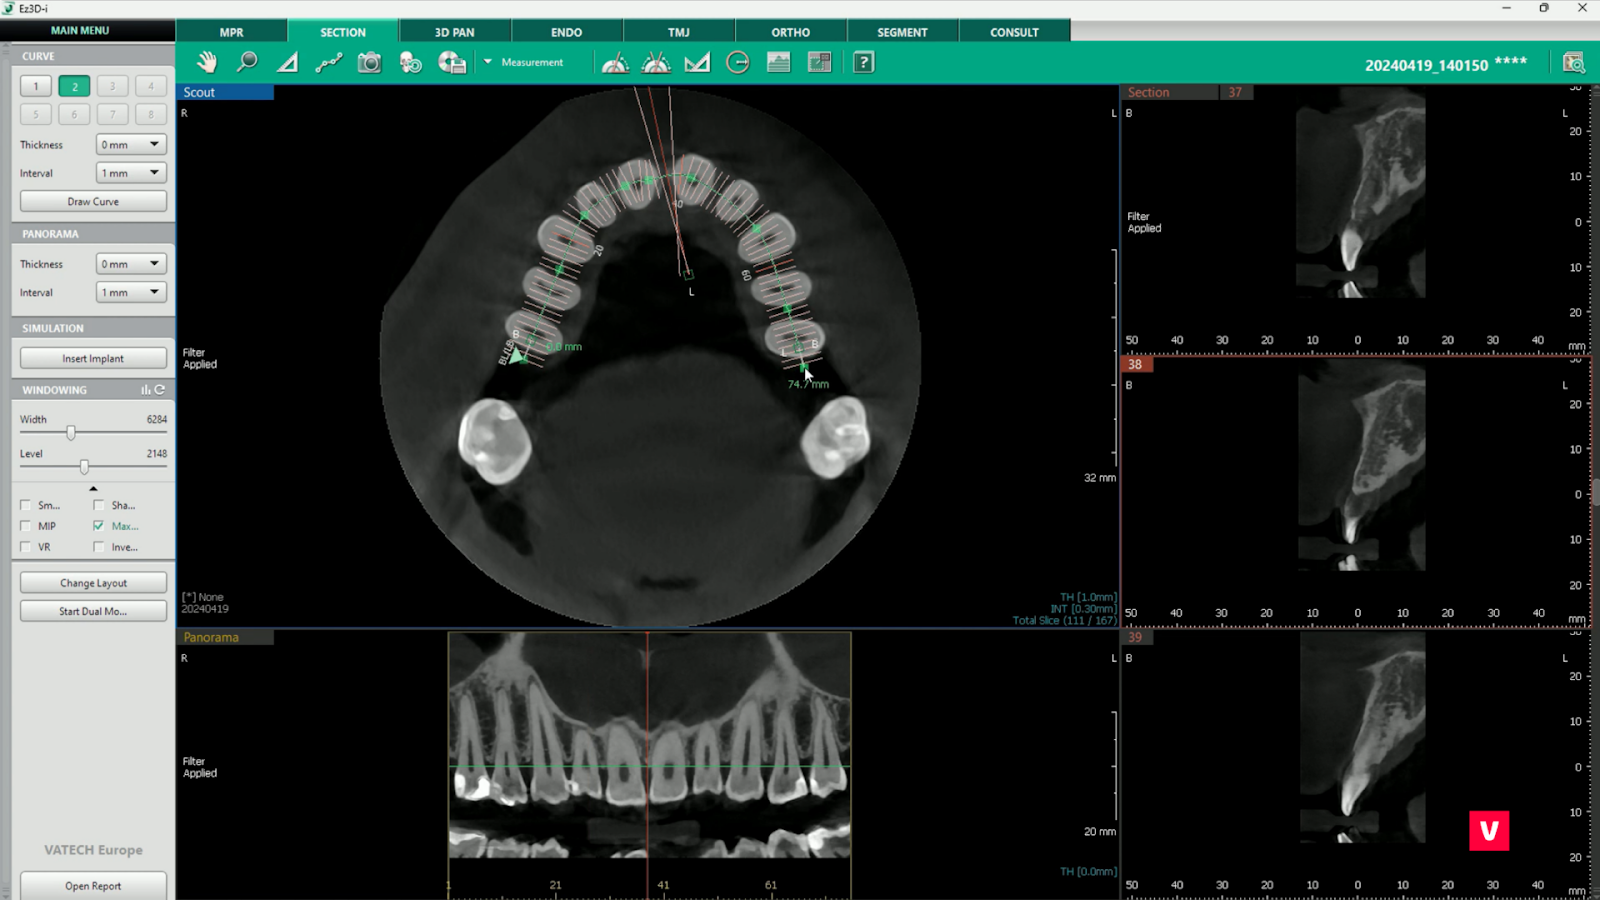

1. Reconstrucția unei secțiuni 2D de-a lungul arcadei dentare

1.Reconstrucția unei secțiuni 2D

Tabul SECTION poate oferi o mulțime de informații utile de diagnosticare. Nu numai că oferă o perspectivă amănunțită asupra dinților, dar ajută și la găsirea canalului mandibular și, prin urmare, este de mare ajutor în procesul de plasare a implanturilor.

Pentru a începe procesul de reconstrucție se folosește funcția „Draw Arcade”. Acest instrument ne ajută la reconstrucția zonelor dorite deoarece, spre deosebire de funcția MPR, unde imaginile sunt realizate conform liniilor prestabilite, putem determina singuri linia arcadei.

Dacă folosim și funcția care ne permite să reglăm grosimea imaginii arcadei, nu vom rata niciun detaliu oricât de mic despre starea dintelui. De asemenea, putem verifica ușor și sigur canalul mandibular inferior.

Procesul de desenare a arcadei este foarte simplu datorită opțiunii de a adăuga elemente vizuale, de a ajusta lungimea și de a o muta în poziția dorită.

În cazul pacientului al cărui studiu de caz îl analizăm, tăierea în plan coronal a evidențiat imediat fractura dintelui dureros, în timp ce imaginea OPG normală nu a putut evidenția problema la fel de clar.

Astfel, datorită funcției SECTION, medicul stomatolog a economisit timp și a obținut un diagnostic corect.